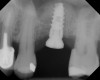

The implant is then delivered and should be well stabilized in the bone. If there is any mobility of the implant, it can either be placed a little deeper (if there is enough native bone) or the implant can be removed and the procedure aborted, in which case it would be a two-stage procedure. This should rarely occur with the tapered designed implant, even with only 2 mm of native bone. Using a bone-level platform-shifting implant (or a tissue-level designed implant) is critical, as the hard and soft tissue will establish a biologic width. If an external hex type of implant is used and the shoulder is placed at the bone level, an expected bone loss of 1.5 mm to 2 mm will occur.24 Figure 10 shows proper bone-level implant depth placement with a platform-shifting design. In this case, a 3-mm healing abutment was placed at the time of surgery to avoid a secondary uncovering surgery, but an implant-level healing abutment could have been placed instead. As can be seen, there was only about 2 mm to 3 mm of native bone height. The membrane was raised about 8 mm to 9 mm. Comparing the radiograph on the day of surgery (Figure 10) to the 6-month postoperative radiograph (Figure 11) shows no loss of native bone, as well as the positive change in appearance of the grafted bone. The 3.5-month CBCT scan (Figure 12) shows good healing of the bone with no coronal bone loss. With minimal native bone present, as in this case, the use of a non-platform-shifting or non-tissue-level implant design could be problematic. After 1.5 mm to 2 mm of crestal bone loss, an external hex designed implant could develop instability with possible implant failure. If a non-tapered implant is used and bone loss occurs during healing, migration of the implant into the sinus could potentially occur. The surgeon can use either a healing abutment or implant-level closure screw over the implant shoulder. With patients who tend to use their tongues to explore or play with the area, or if the area is under a removable partial denture, a closure screw is recommended.

A 74-year-old man presented with only about 2 mm to 3 mm of native bone below the sinus in the No. 14 position (Figure 13). The composite graft used was an approximately 50:50 mixture of DFDBA (Bio-Oss®, Geistlich Biomaterials, www.bio-oss.com) with the addition of about 40% calcium sulfate by volume (Figure 14). The implant placed (Figure 15) was a 10-mm long, rough-surfaced, platform-shifting implant (tapered 4.2 mm to 2.8 mm), and the sinus was raised about 8 mm. The postoperative radiograph taken at 4 months (Figure 16) showed some shrinkage of the graft, but no demarcation of the old sinus floor in the area.